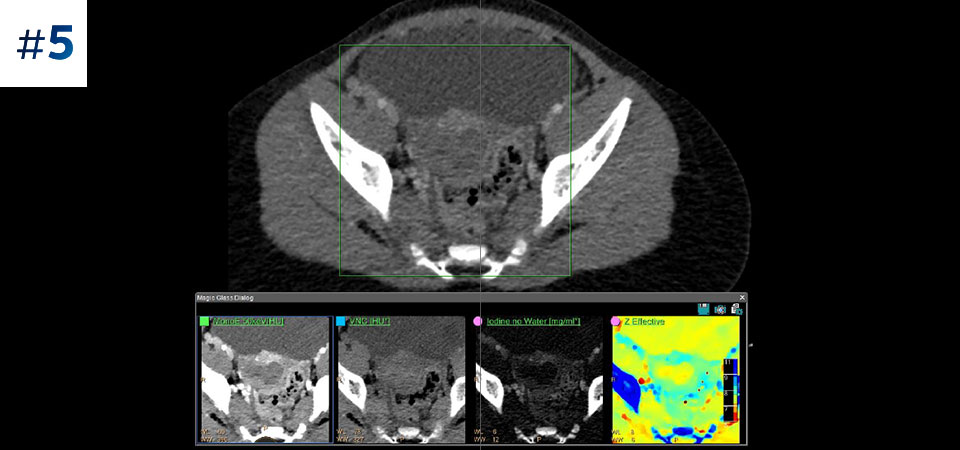

Across patient types Benefits a wide range of patient types from pediatric to bariatric.